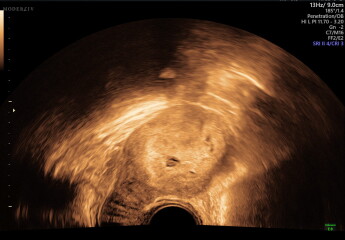

scan at 5 weeks 3 days, no heartbeats but possible twins (picture)

she then said the weird thing was that she thought she could see two sacs. she said she thought she saw it on the external scan & then on the internal when she checked. but she said it was hard to recreate the images again & then one was too blurry to see anything. from what she could measure on one it measured as 5 week2 days so pretty in line with what i thought. I have never even considered multiples, zero history in my family & I am not so old so i was shocked. she seemed very unsure but again dont know how careful she was being then said i would have to come in a weeks time, & if i needed anything in the meantime let her know

Ive attatched pictures if anyone is any good at reading, i dont feel ready to talk to anyone in real life about this yet